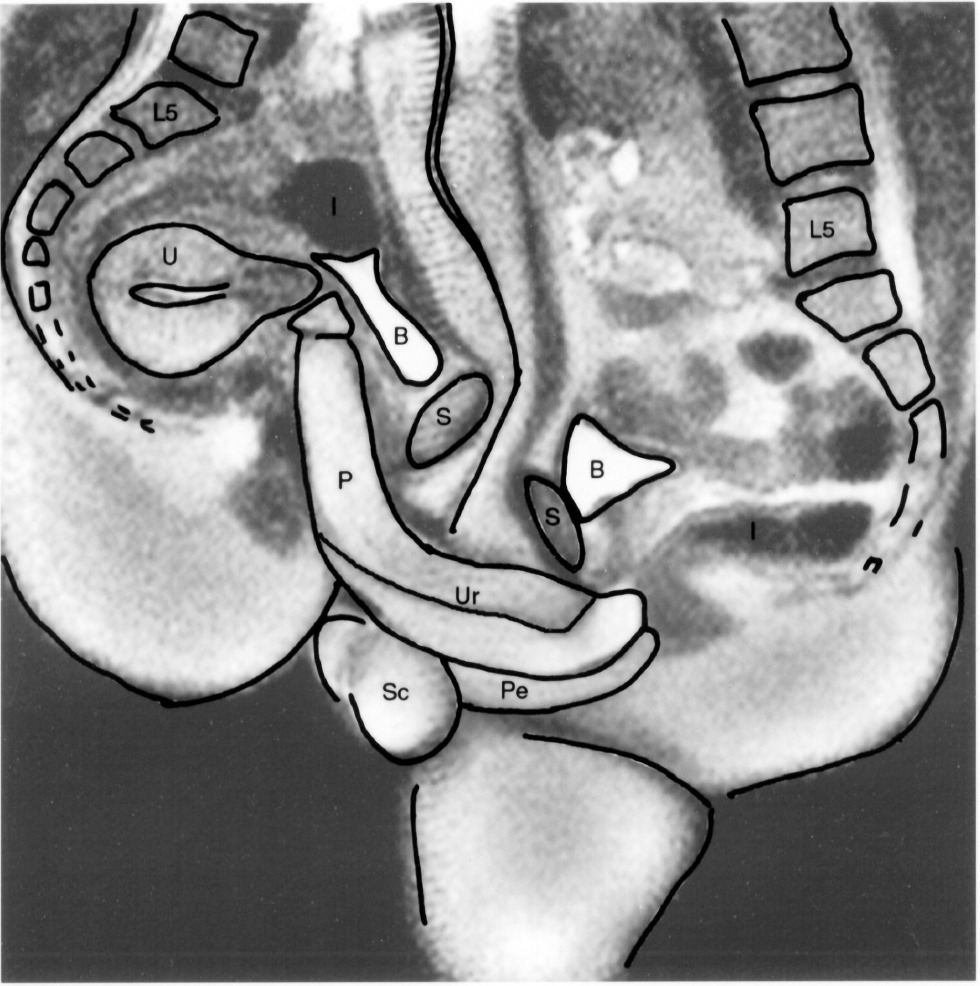

A cross-sectional diagram of the sex act in porn

Anatomy of sexual intercourse

Anatomy of sexual intercourse in the section